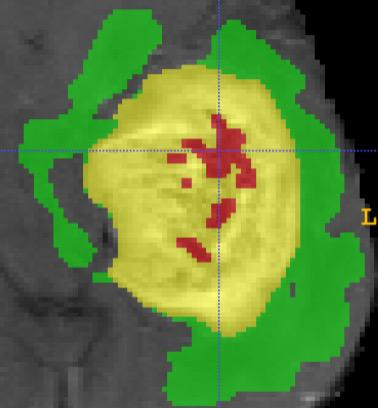

As information sources are usually imperfect, it is necessary to take into account their reliability in multi-source information fusion tasks. In this paper, we propose a new deep framework allowing us to merge multi-MR image segmentation results using the formalism of Dempster-Shafer theory while taking into account the reliability of different modalities relative to different classes. The framework is composed of an encoder-decoder feature extraction module, an evidential segmentation module that computes a belief function at each voxel for each modality, and a multi-modality evidence fusion module, which assigns a vector of discount rates to each modality evidence and combines the discounted evidence using Dempster's rule. The whole framework is trained by minimizing a new loss function based on a discounted Dice index to increase segmentation accuracy and reliability. The method was evaluated on the BraTs 2021 database of 1251 patients with brain tumors. Quantitative and qualitative results show that our method outperforms the state of the art, and implements an effective new idea for merging multi-information within deep neural networks.